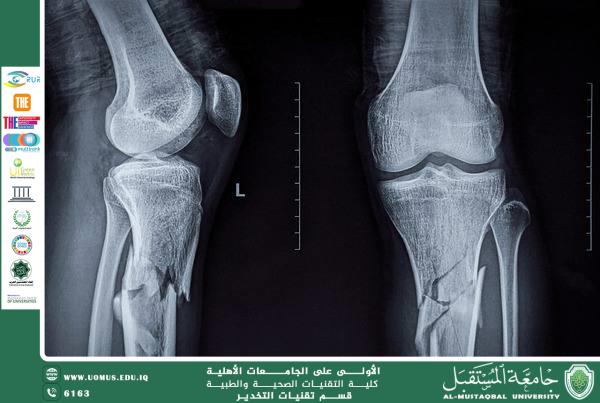

Step-by-Step Initial Treatment Step 1: Ensure Safety and Assess the Situation • Check for Danger: Make sure the area is safe for you and the victim (e.g., traffic, fire, falling objects). • Call for Help: If the person is seriously injured, has multiple fractures, or is unresponsive, call emergency services immediately. • Do Not Move the Person: Unless there is an immediate threat to life (e.g., a burning vehicle), avoid moving the victim. Moving someone with a possible spinal or neck injury can cause permanent paralysis. Step 2: Perform a Primary Survey (Check for Life-Threatening Issues) Follow the DRSABCD protocol: • Danger: Ensure the scene is safe. • Response: Check if the person is conscious. Tap their shoulder and ask, “Are you okay?” • Send for Help: If unresponsive, call emergency services. • Airway: Make sure the airway is clear. • Breathing: Check for normal breathing. • CPR: If the person is not breathing, start CPR if trained. • Defibrillation: Use an AED if available and required. Step 3: Look for Signs of a Fracture Once life-threatening issues are managed, check for: • Deformity: Limb looks bent or in an abnormal position. • Swelling and Bruising: Around the injured area. • Inability to Move the Limb: Movement is extremely painful or impossible. • Visible Bone: Bone protruding through the skin (open/compound fracture). • Grating Sound: A grinding sensation when the limb is touched or moved (crepitus). • Severe Pain and Tenderness: Especially with movement. Step 4: Provide General Care for the Fracture 1. Control Bleeding and Cover Wounds (For Open Fractures) • Apply gentle pressure around the wound, not on the exposed bone. • Cover the wound with a sterile dressing or clean cloth. • DO NOT attempt to push the bone back inside. 2. Immobilize the Injury • Prevent movement of the broken bone and the joints above and below it. • Use available materials such as a board, rolled newspaper, stick, or even an umbrella as a splint. • Pad the splint for comfort using cloth or towels. • Secure the splint with bandages or strips of cloth—tight enough to hold but not cut circulation. 3. Apply a Sling (For Arm Injuries) • Use a triangular bandage or a large cloth. • Keep the hand slightly elevated above the elbow. 4. Manage Shock • Lay the person down, keep them warm with a blanket, and elevate their legs (unless a leg, hip, or spine injury is suspected). 5. Comfort and Reassure • Stay with the person until help arrives. • Keep them calm and still. What NOT To Do (Critical Mistakes) • DO NOT straighten or “reset” the bone. • DO NOT move the person unnecessarily, especially if a head, neck, or spinal injury is suspected. • DO NOT give food or drink (in case surgery is needed). • DO NOT apply a tourniquet unless trained and bleeding is uncontrollable. • DO NOT tie bandages tightly over the fracture site. Summary: Key Priorities at the Scene 1. Call emergency services. 2. Do not move the victim. 3. Control bleeding (for open fractures). 4. Immobilize the injured area with a splint or sling. 5. Treat for shock and provide reassurance. Professional medical care—including X-rays, casting, or surgery—will be provided by emergency responders and hospital staff. Your role at the scene is to provide essential first aid to prevent further injury. Talib Chichan Al-Mustaqbal University The First University in Iraq